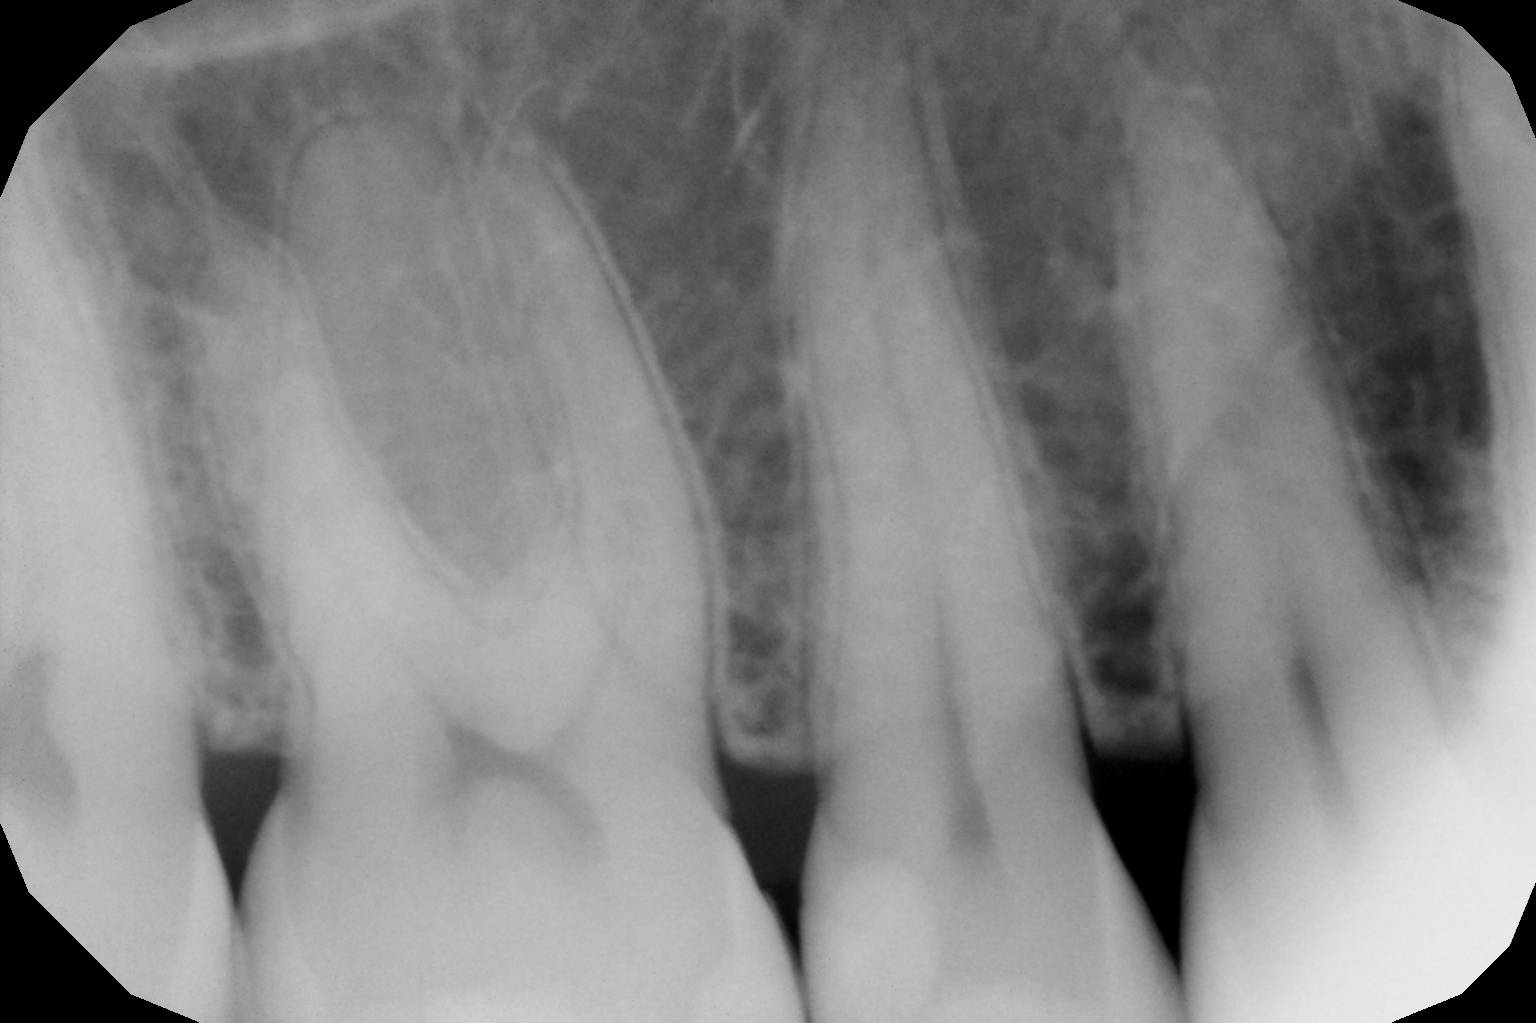

foto 12 Aspetto radiografico